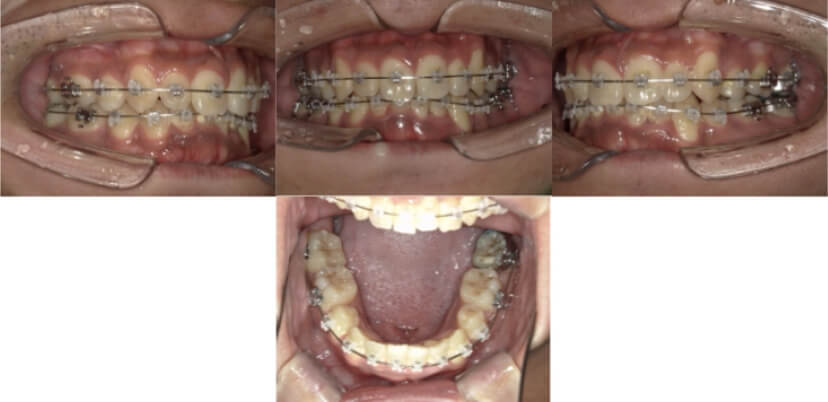

上下顎叢生(上下の前歯のガタガタ)のケースです。

装置はラビアル(上下表側)で、上下顎の小臼歯を4本抜歯を行っています。抜歯したスペースを使って、上下の前歯の後方移動と叢生(ガタガタ)の改善を行っています。

主訴 歯並びが悪く、舌を噛んでしまうのを治したい。

年齢・性別 27歳 男性

お住まいの地域 東京都大田区

治療方針 抜歯スペースを利用して上下前歯の叢生(ガタガタ)の改善

抜歯部位 上下顎左右第一小臼歯

使用装置 ラビアル(上下表側)、顎間ゴム

治療期間 3年1か月

治療回数 30回

治療経過